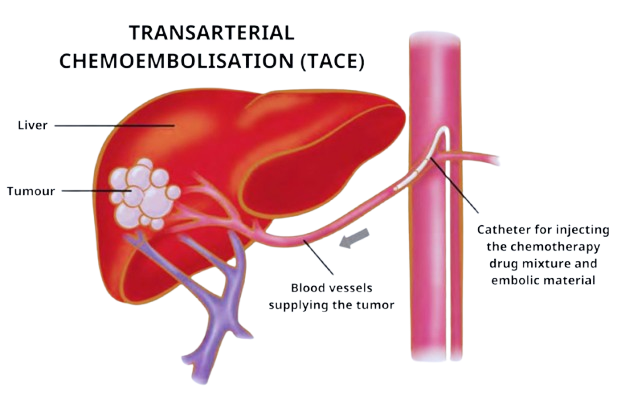

Transarterial Chemoembolization (TACE) is a minimally invasive, targeted treatment for liver cancer (especially Hepatocellular Carcinoma) that combines chemotherapy with vessel blockage. By injecting chemo drugs directly into the liver tumor’s artery, it…